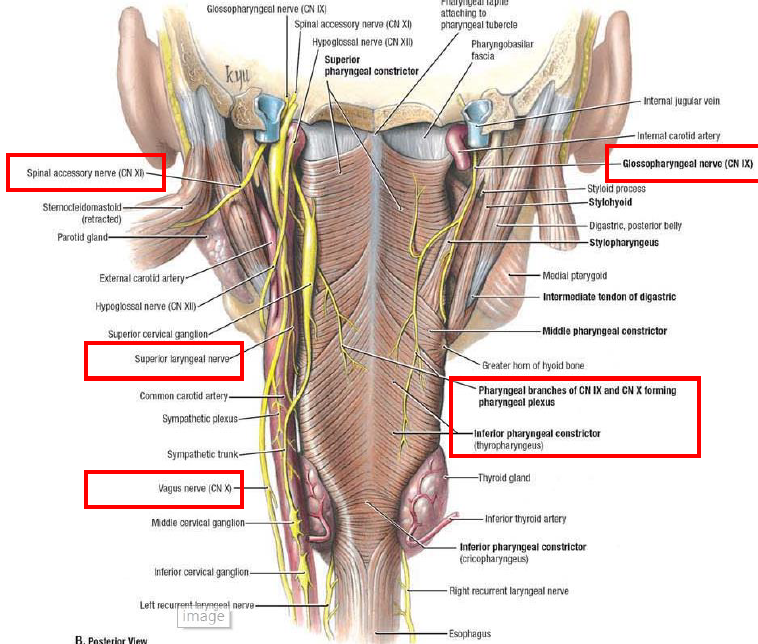

CN IX

Motor

- Stylopharyngeus m.

- Lesser petrosal n.(Parasymphysis)

- 支配Parotid g.的副交感節前神經

Sensor

- Tympanic n.

- 中耳、鼓膜內面、耳咽管(Eustachian)

- Sinus n.

Terminal

- Pharyngeal br.(with CN X)

- Mucosa of oropharynx

- Tonsillar br.

- Palatine tonsil

- Lingual br.

- 舌頭後1/3味覺、一般感覺

分隔ECA,ICA

CN X

Structure

- common carotid a. 外側,蓋在 thyrocervical trunk 上

- recurrent laryngeal n.沿 tracheoesophageal groove 攀升(就是食道和氣管中間),接觸 medial thyroid gland,向內鑽到 inf. constrictor,進入 larynx,同時支配感覺與運動

Pharyngeal br.

- Pharynx (除了 Stylopharyngeus)

- Sup. laryngeal n.

- Internal br.(Internal laryngeal n.)

- Laryngopharynx

- Larynx (Vocal fold 以上)

- 舌根、Epiglottis 味覺

- External br.

- Cricothyroid m.

- Recurrent laryngeal n.

- 過Cricothyroid joint改叫Inf. laryngeal n.

- 支配所有軟骨間肌,除了 Cricothyroid m.

- 假聲摺以下的喉部黏膜感覺

recurrent laryngeal n.

- left: arch of aorta

- right: Subclavian a.

CN XI

- Spinal root(C1-C5)混合

- 向後支配SCM, Trapezius